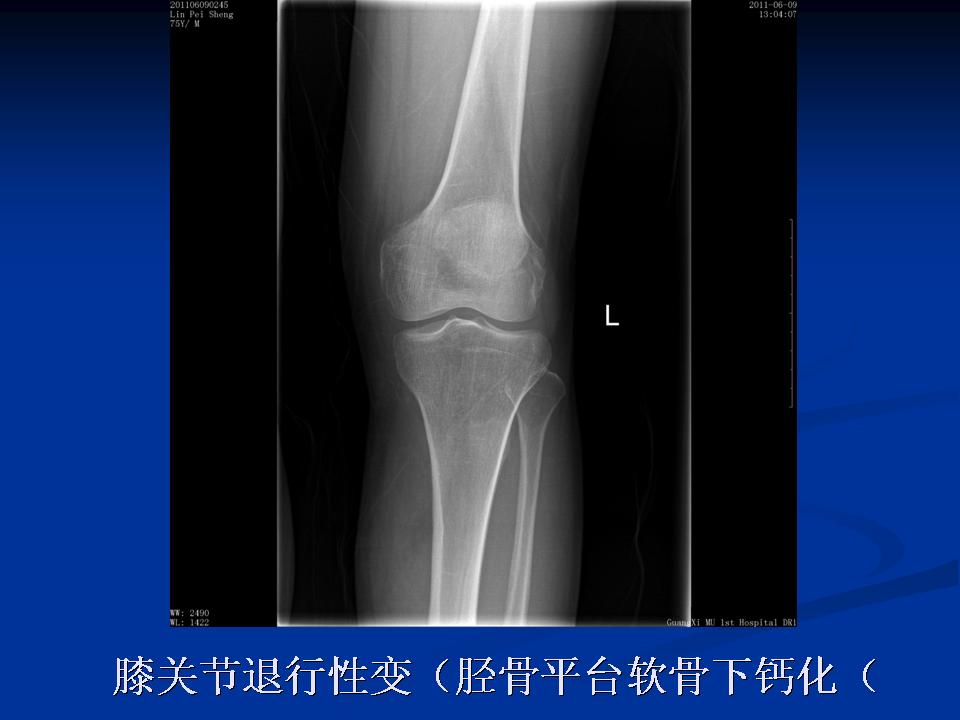

膝关节退行性变(胫骨平台软骨下钙化)